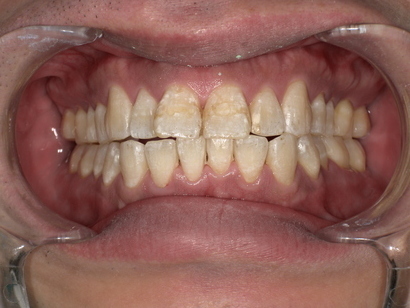

5. After|治療後の変化は?(自然な白さが復活)

クリーニング後、鏡を確認された患者様は、

「え、こんなに白くなるんですね!」

と驚かれていました。

施術後の特徴:

-

茶色くくすんでいた歯が明るい白さに戻った

歯と歯の間の黒い汚れが消えた

歯の表面がツルツルになり清潔感UP

口元の印象が若返った

1回の施術でこれだけ変化が出るのは、専門的な機器で歯石と着色を同時に除去しているためです。